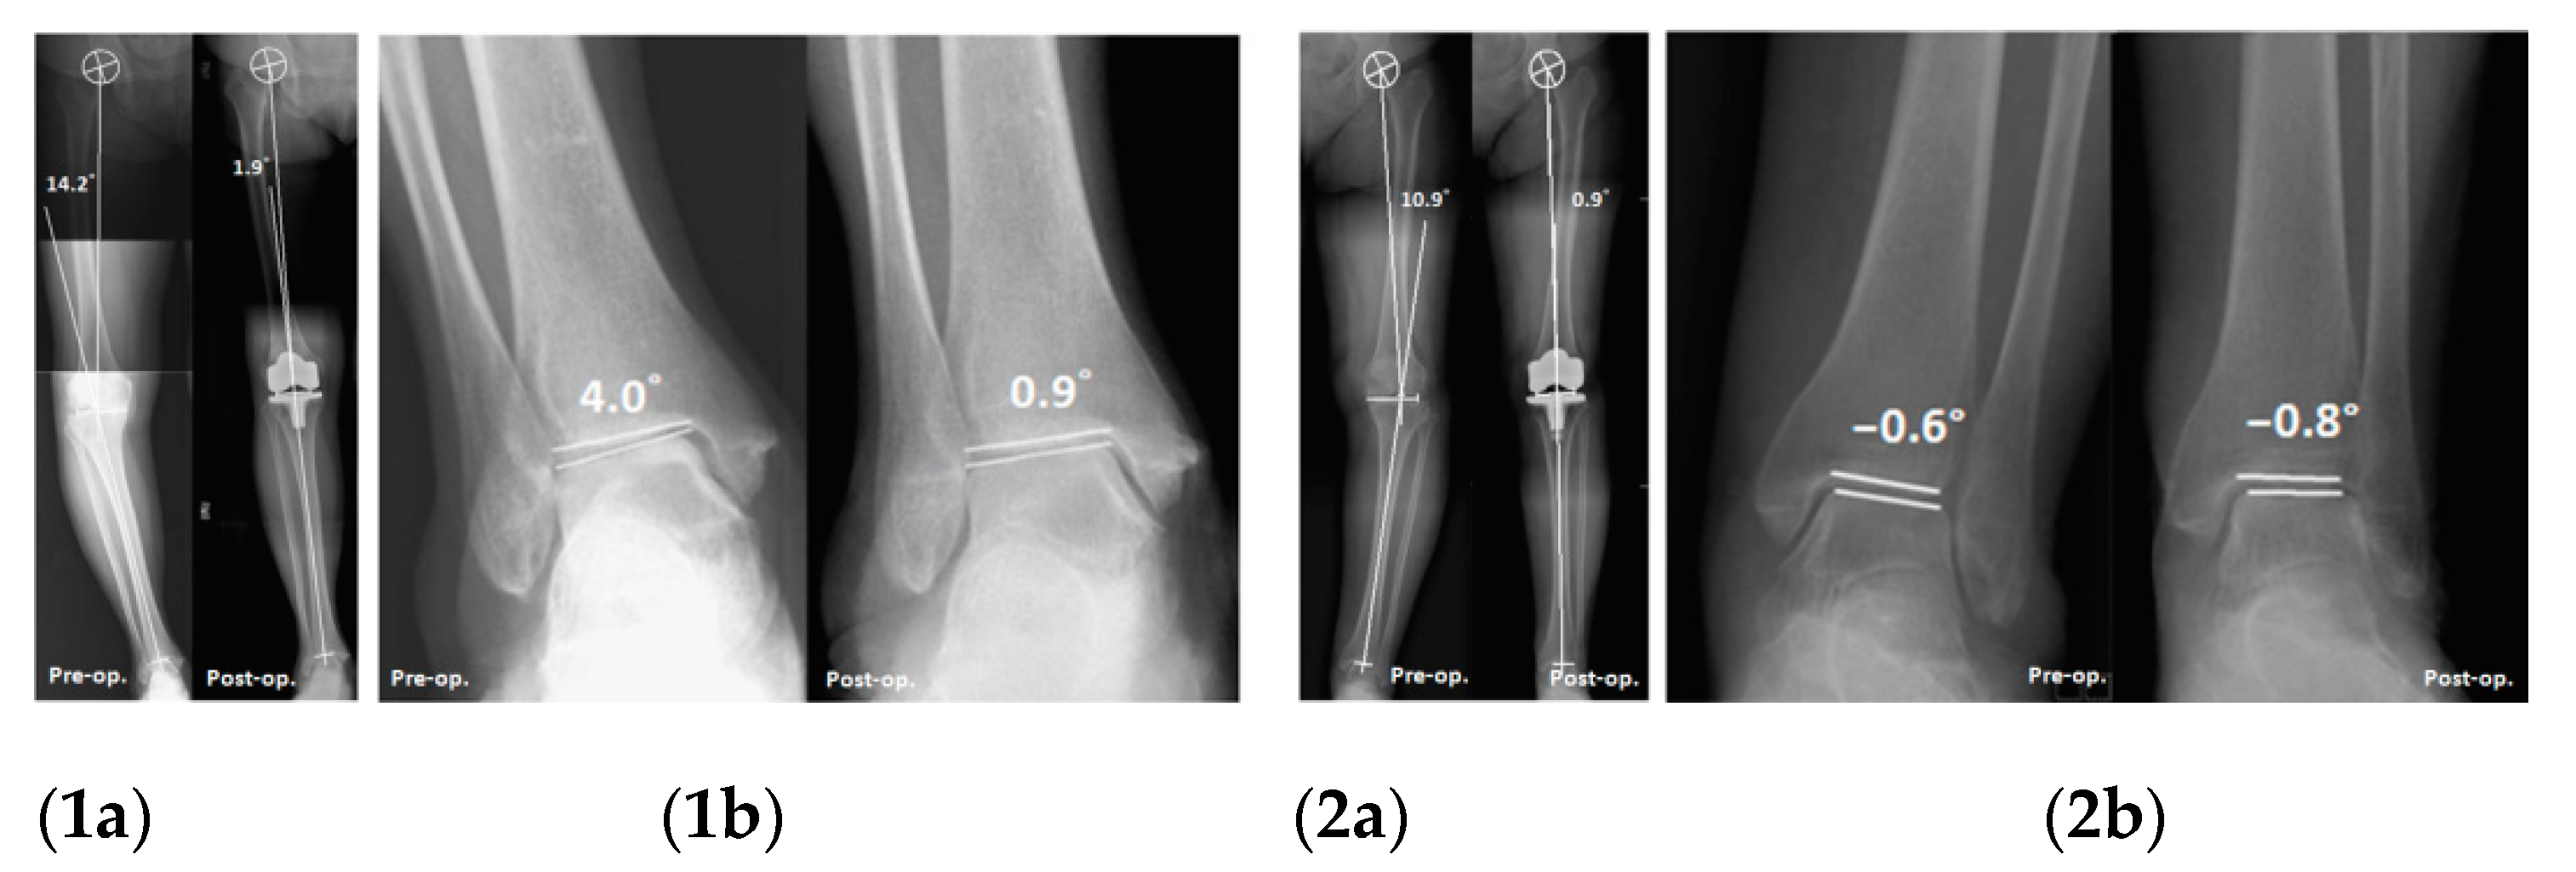

| Valgus group | HKA (°) | 10.5 [3.6, 12.3] | 2.7 [0.5, 5.0] | 0.001 |

| PGA (°) | −6.6 [−8.8, −2.3] | −1.6 [−3.9, 1.8] | 0.017 | |

| TGA (°) | −5.2 [−7.0, −1.8] | −0.1 [−3.1, 2.6] | 0.008 | |

| PTA (°) | −1.3 [−1.7, −0.6] | −0.9 [−1.4, 0.0] | 0.197 | |

| Varus group | HKA (°) | 10.4 [6.9, 14.3] | 2.3 [0.9, 4.8] | <0.001 |

| PGA (°) | −5.4 [−9.1, −1.2] | −1.1 [−4.5, 3.2] | <0.001 | |

| TGA (°) | −6.8 [−10.9, −3.1] | −1.7 [−5.5, 2.6] | <0.001 | |

| PTA (°) | 1.2 [0.5, 2.5] | 0.3 [−0.2, 1.6] | <0.001 | |